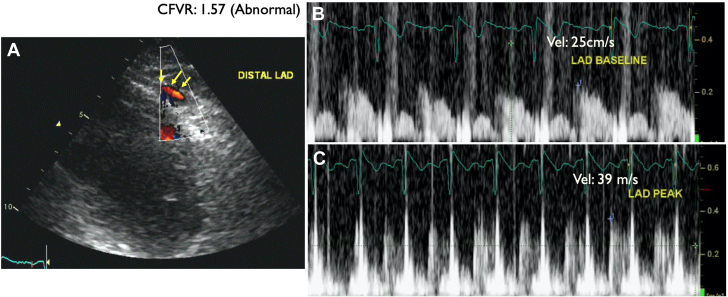

A 64-year-old woman with coronary calcification on chest computed tomography scan at the time of COVID-19 infection was referred for elective DSE. She had atypical chest pain and was on metoprolol for occasional palpitation. The DSE was terminated at the end of protocol at 92% of age-predicted maximal heart rate with no symptoms (30 μg/kg/min and 0.10 mg atropine in addition to handgrip exercise; rate-pressure product, 19,140 mm Hg·beats/min). The resting echocardiogram showed no RWMA, and all segments of the left ventricle augmented well during low dose and remained hyperdynamic at peak. The CFV in the distal LAD was 23 cm/s and 36 cm/s at baseline and peak, respectively, in keeping with reduced CFVR (1.57) (Figures 13 and 14, Video 5). After the DSE, the patient was recommended ICA, but she refused it. The patient was recommended risk factor management and symptom control with antianginal medication for CMD.

Figure 14.

Patient 4: Coronary Flow Velocity by Doppler Echocardiography

Coronary flow velocity by Doppler echocardiography in the distal left anterior descending coronary artery (LAD) (yellow arrows indicate distal LAD color Doppler flow in diastole). LAD flow velocity reserve (CFVR) = baseline CFV/peak CFV: 39/25 = 1.57 (abnormal).